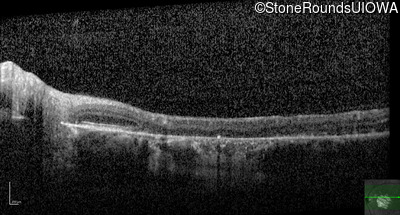

Optical Coherence Tomography - Right - 20/125

Exemplar / OCT Stack